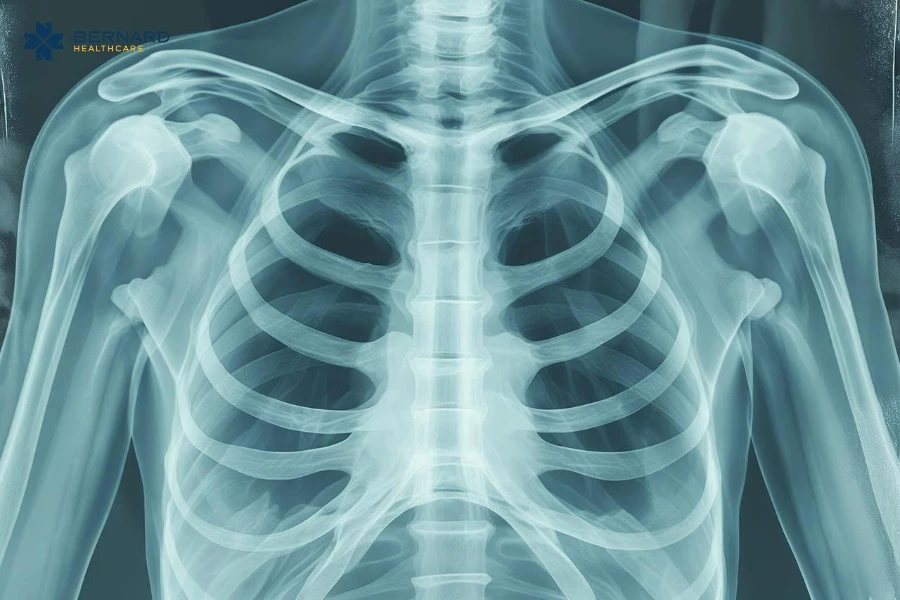

U trung thất là thuật ngữ chỉ những khối bất thường (u, nang, mô tăng sinh…) xuất hiện trong trung thất - vùng nằm giữa hai phổi, nơi chứa tim, màng ngoài tim, khí quản, phế quản, tĩnh mạch chủ, động mạch lớn và nhiều dây thần kinh quan trọng. Nếu các bất thường không được phát hiện và điều trị kịp thời có thể dẫn đến những biến chứng nguy hiểm đến tính mạng.

Trung thất là khu vực có cấu trúc giải phẫu phức tạp nhất trong lồng ngực, nơi tập trung hàng loạt cơ quan sống còn như tim, màng ngoài tim, khí quản, phế quản, tĩnh mạch chủ trên, động mạch phổi và nhiều dây thần kinh quan trọng.

Khác với các vị trí khác trong cơ thể, trung thất không có khả năng “giãn nở” để tạo khoảng trống. Do đó, các tổn thương xuất hiện tại đây, đặc biệt là những tổn thương có kích thước lớn ở trung thất giữa, sát màng ngoài tim đều tiềm ẩn nguy cơ gây biến chứng nghiêm trọng.

Một trong những thách thức lớn nhất của tổn thương trung thất là đa dạng bản chất: khối nang, khối đặc, u mỡ, u thần kinh, lymphoma, u tuyến ức hoặc di căn. Trên X-quang ngực, những tổn thương này thường chỉ hiện như một vùng mờ, không đủ thông tin để phân biệt.

Do đó, CT Scan đa lát cắt, MRI chuyên sâu và kinh nghiệm phân tích hình ảnh bởi bác sĩ/chuyên gia chẩn đoán hình ảnh là yếu tố bắt buộc trong việc xác định chính xác loại tổn thương, đánh giá ranh giới và mức độ chèn ép, nhận diện nguy cơ xâm lấn, lên kế hoạch điều trị phù hợp và quyết định có cần sinh thiết hay theo dõi định kỳ.